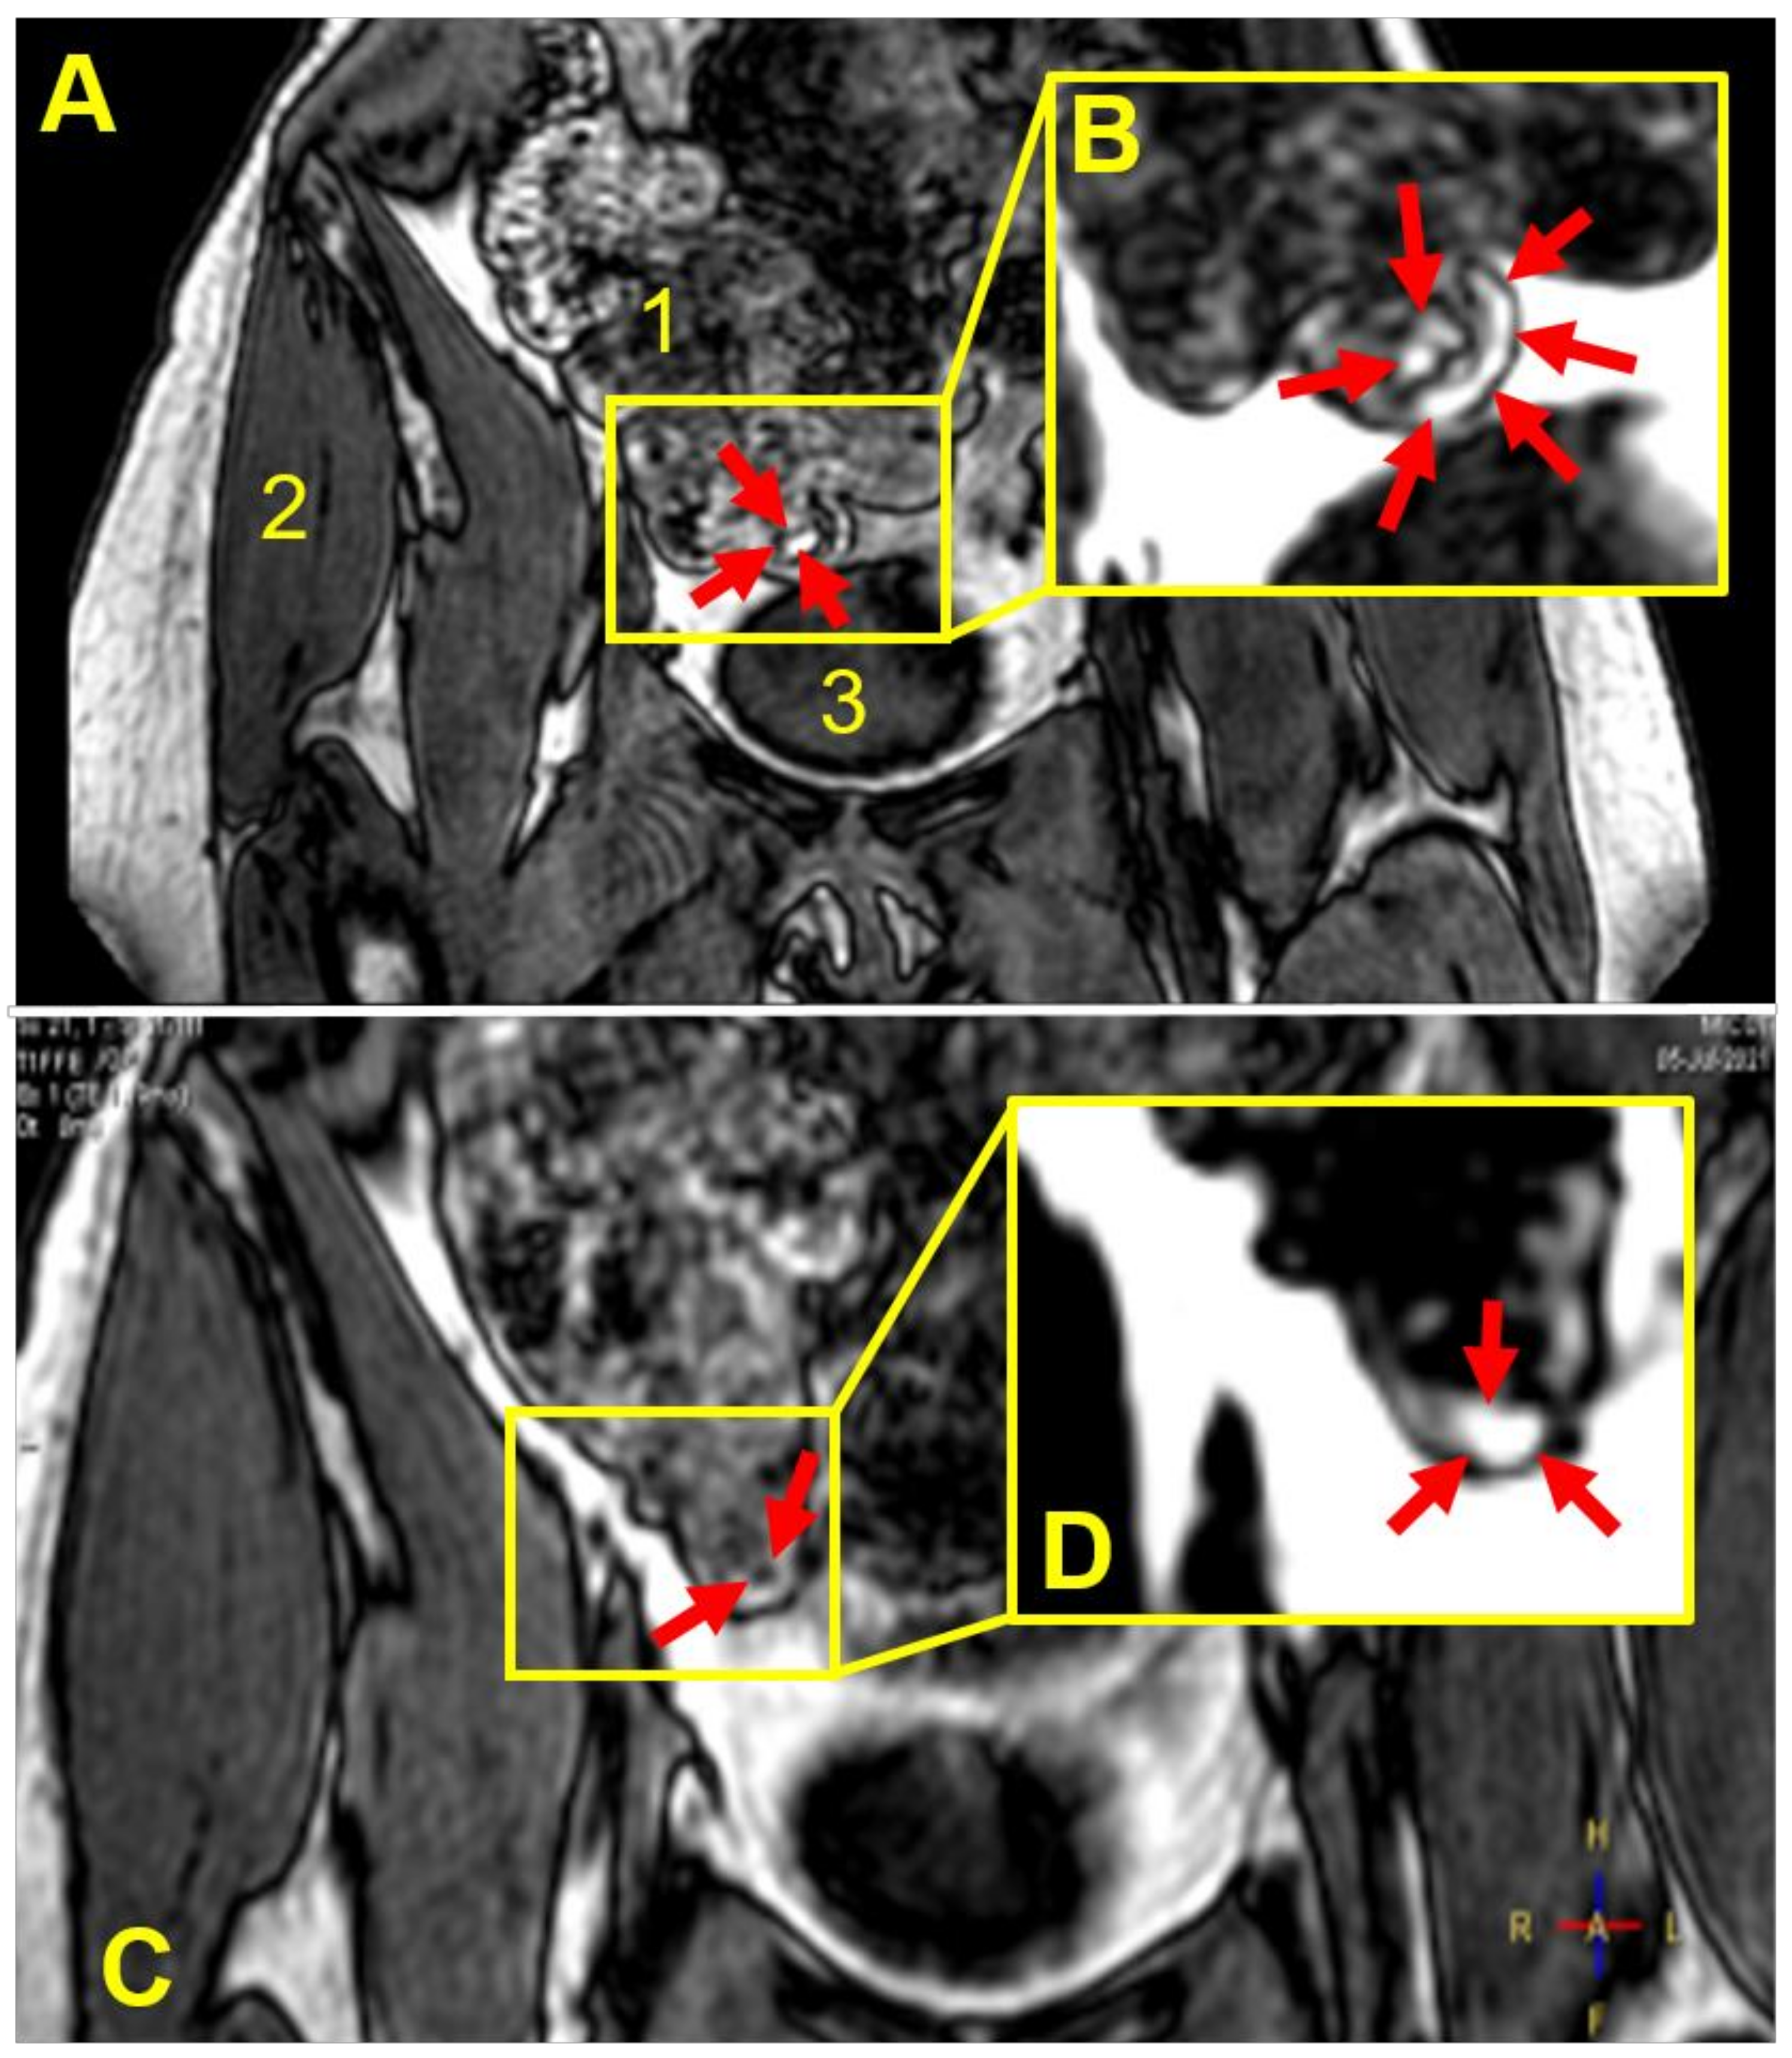

| Participant | Weight Gain (mg) a | Weight Gain Per Surface Area (mg/mm2) | Gastrointestinal Location and Integrity of the Capsule at the Different Imaging Time Points (min) | |||||||

|---|---|---|---|---|---|---|---|---|---|---|

| 45 | 90 | 135 | 180 | 225 | 270 | 315 | 360 | |||

| 1 | 9.2 ± 0.8 | 0.02 | Stomach | Stomach | Stomach b | NO c | NO | NO | NO | NO |

| 2 | 18.2 ± 1.2 | 0.04 | Stomach | Stomach | Duodenum | Duodenum | Term ileum | NO | NO | d |

| 3 | 18.2 ± 1.2 | 0.04 | Stomach | Stomach | Term ileum | Asc colon | Hep flexure | Hep flexure | Hep flexure | Hep flexure |

| 4 | 18.2 ± 1.2 | 0.04 | Stomach | Jejunum | Jejunum | Jejunum | Term ileum | Term ileum | Term ileum | NO |

| 5 | 18.2 ± 1.2 | 0.04 | Stomach | Jejunum | Cecum | Cecum | Asc colon | Asc colon | NO | Hep flexure |

| 6 | 18.2 ± 1.2 | 0.04 | Stomach | Stomach | Term ileum | Term ileum | NO | NO | NO | NO |

| 7 | 18.2 ± 1.2 | 0.04 | Stomach | Jejunum | Jejunum | Term ileum | Term ileum | NO | NO | NO |

| 8 | 36.0 ± 5.2 | 0.08 | Stomach | Jejunum | Term ileum | Cecum | NO | NO | shade | |

| 9 | 52.6 ± 9.7 | 0.11 | Stomach | Duodenum | Term ileum | Hep flexure | Hep flexure | Trans colon | Trans colon | |

| 10 | 52.6 ± 9.7 | 0.11 | Stomach | Stomach | Duodenum | Duodenum | NO | NO | ||